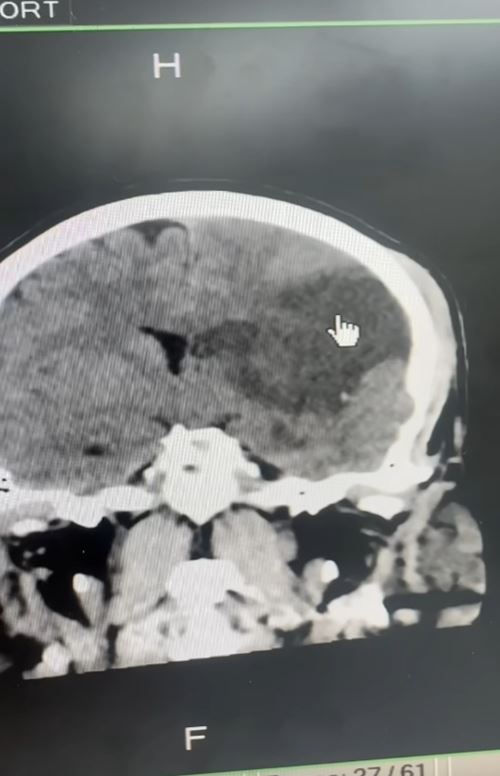

วันที่ 7 พฤษภาคม 2568 เฟซบุ๊ก หมอประชาผ่าตัดสมอง มีการเล่าเคสสามีปวดหลัง เลยให้ภรรยานวด ผลสุดท้ายเลวร้ายสุดคาดคิด เรื่องมีอยู่ว่า หลังจากกินอาหารเย็นก็ให้ภรรยานวดก่อนนอน รู้สึกเคล็ดกว่าเดิม ตื่นเช้ามาแขนขาอ่อนแรงด้านขวา และไม่พูด ทั้งที่ไม่มีโรคประจำตัว

เมื่อไปหาหมอ พบว่า สมองตายเกินกว่า 8 ชั่วโมง เนื่องจากเส้นเลือดที่คอปริแตก ลิ่มเลือดไปอุดตัน ทางรักษาคือ เปิดกะโหลกเพื่อลดความดันสมอง ดังนั้นห้ามกดเส้นเลือดด้านหน้าลำคอเด็ดขาด เพราะเสี่ยงปริจนเส้นเลือดอุดตันได้